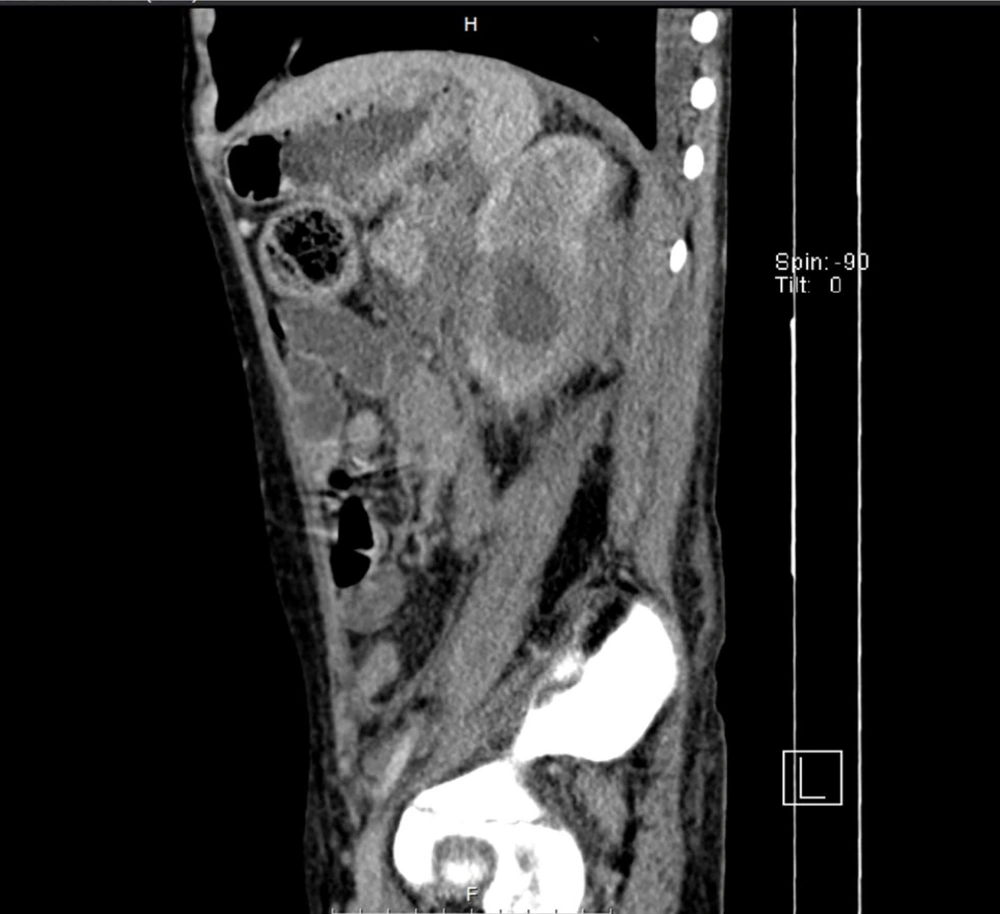

2.4.3. Spiral Abdominal CT Scan

A large retroperitoneal mass encasing the aorta, IVC, superior mesenteric artery (SMA), and ureters (Figure 1). Thrombosis extended into the IVC and right iliac vein, with moderate bilateral hydronephrosis.

In this case, the imaging findings introduced further complexity to the diagnostic process. The presence of a large retroperitoneal mass, bilateral hydronephrosis, and vertebral lesions raised suspicion for lymphoma, highlighting a common diagnostic pitfall in GIB cases (10, 14). Hypermetabolic activity observed in the L3-L5 vertebrae and proximal radius initially raised concerns for potential metastatic disease. These findings align with documented cases where GIB mimics neoplastic or granulomatous diseases, often delaying appropriate treatment (15, 16). Unresponsive symptoms, coupled with inconclusive imaging findings, prompted an exploratory laparotomy, underscoring the challenges in diagnosing such a rare condition (7).